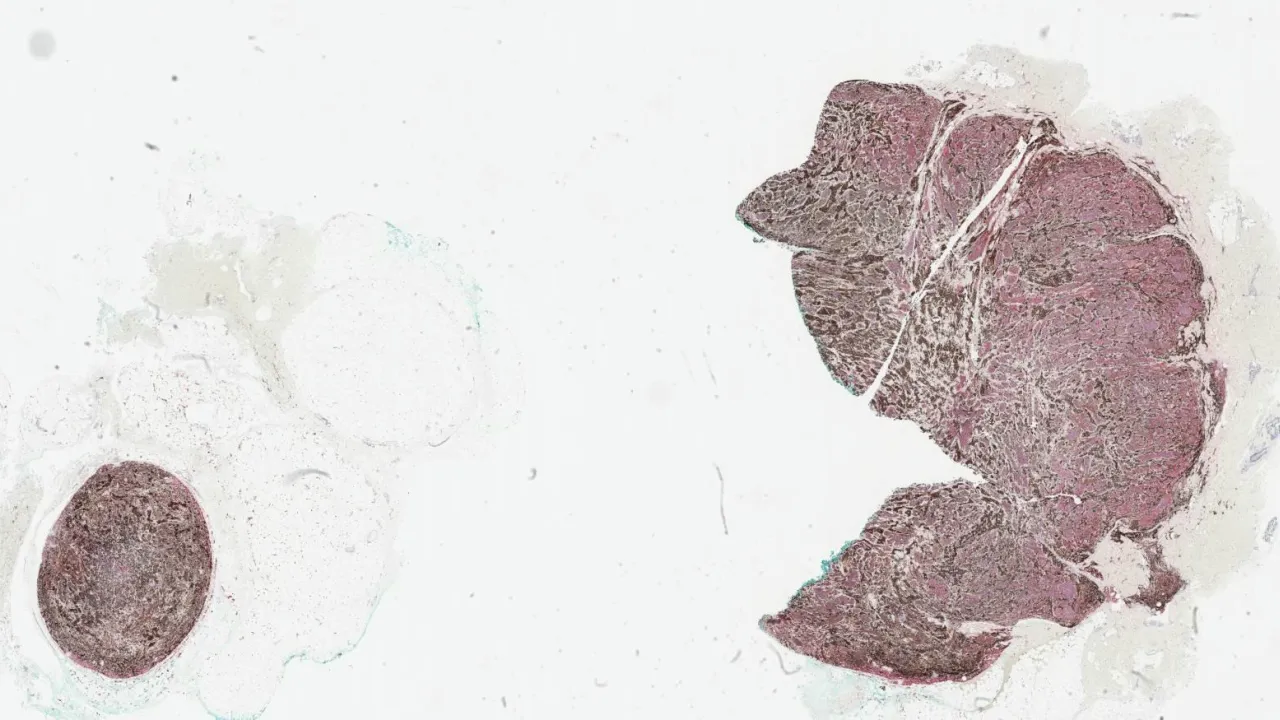

Testis, Mixed germ cell tumour, CD30 stain